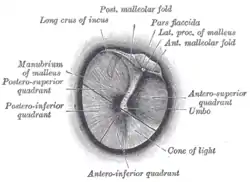

Right eardrum as seen through a speculum | |

Regions

The eardrum is divided into two general regions: the pars flaccida and the pars tensa.[3] The relatively fragile pars flaccida lies above the lateral process of the malleus between the Notch of Rivinus and the anterior and posterior malleal folds. Consisting of two layers and appearing slightly pinkish in hue, it is associated with Eustachian tube dysfunction and cholesteatomas.[4]

The larger pars tensa consists of three layers: skin, fibrous tissue, and mucosa. Its thick periphery forms a fibrocartilaginous ring called the annulus tympanicus or Gerlach's ligament.[5] while the central umbo tents inward at the level of the tip of malleus. The middle fibrous layer, containing radial, circular, and parabolic fibers, encloses the handle of malleus. Though comparatively robust, the pars tensa is the region more commonly associated with perforations.[6]

Umbo

The manubrium (Latin: handle) of the malleus is firmly attached to the medial surface of the membrane as far as its center, drawing it toward the tympanic cavity. The lateral surface of the membrane is thus concave. The most depressed aspect of this concavity is termed the umbo (Latin: shield boss).[7]

When the eardrum is illuminated during a medical examination, a cone of light radiates from the tip of the malleus to the periphery in the anteroinferior quadrant, this is what is known clinically as 5 o'clock.

Chain of ossicles and their ligaments, seen from the front in a vertical, transverse section of the tympanum [tympanic cavity] Right eardrum as seen through a speculum

Right eardrum as seen through a speculum This is a normal left eardrum.